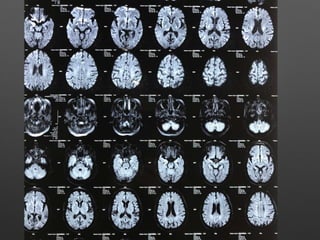

HOPI • Patient wasapparently normal till 5pm 3/2/18, started behaving abnormally like half dressed, with carrying comb and want to go temple, with irrelevant talks. • Relatives observed paucity of left Upper and lower limb, thinking of stroke - took her to near by hospital • Asked for imaging - after imaging she developed 2 episodes of left sided jerky movements of both UL & LL with twitching over the face - lasted for 1-2 min, treated with sedative , Inj. insulin for high CBG - 495 mg/dl and referred here for further management.

Provisional Diagnosis • ?Acuteischemic stroke - left hemiparesis with focal seizures • ? Hyperglycemic encephalopathy • ? Viral encephalitis

Investigations • HB- 14.1gm%- 12.2 • WBC- 15990cells/cumm - 10770, -P 83%, L-9%,M-7% • Platelets - 3.3lakhs - 2.8 • ESR- 63mm/hr • RBS - 267 mg/dl • CUE - N • RFT - N • LFT - N • S.Na - 137, k+ - 3.9, Mg- 2.1, Ca- 9.1, Ph- 3.5, Ammonia- 0.29

• ECG -N • 2DEcho- N • U/S - Abd- Gr I Fatty liver changes